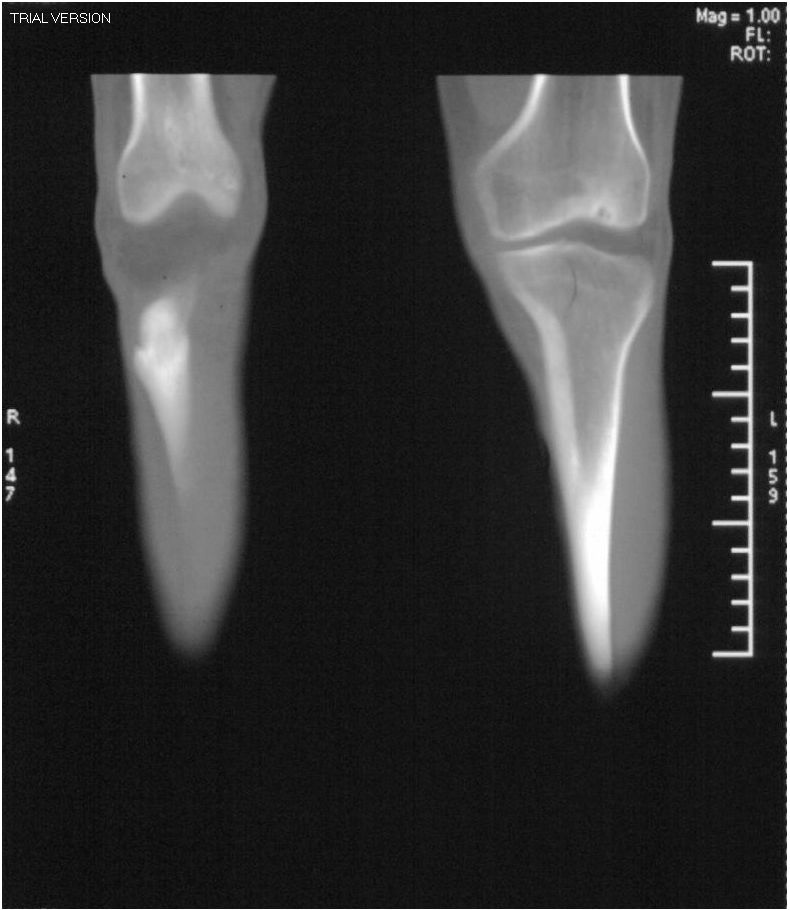

男,42岁。4个月前钢筋钝伤右侧小腿部,当时因无明显外伤,未引起重视。一周后因受伤腿部疼痛,发现肿胀,随后到当地医院进行检查(2008年4月16日)。因未发现骨质异常未引起重视,仅仅进行口服抗生素治疗处理。经过一段时间治疗但未见明显治疗效果在5月29日又进行x线检查,发现有胫骨密度上段密度增高,又进行抗炎治疗,仍未见效果。又在7月3日进行x线检查,仍然报告有胫骨上端密度增高,并建议ct检查。以下是相关检查结果:

该患者到某三级医院进行会诊,并重新作了平片检查,认为畸形性行骨炎: